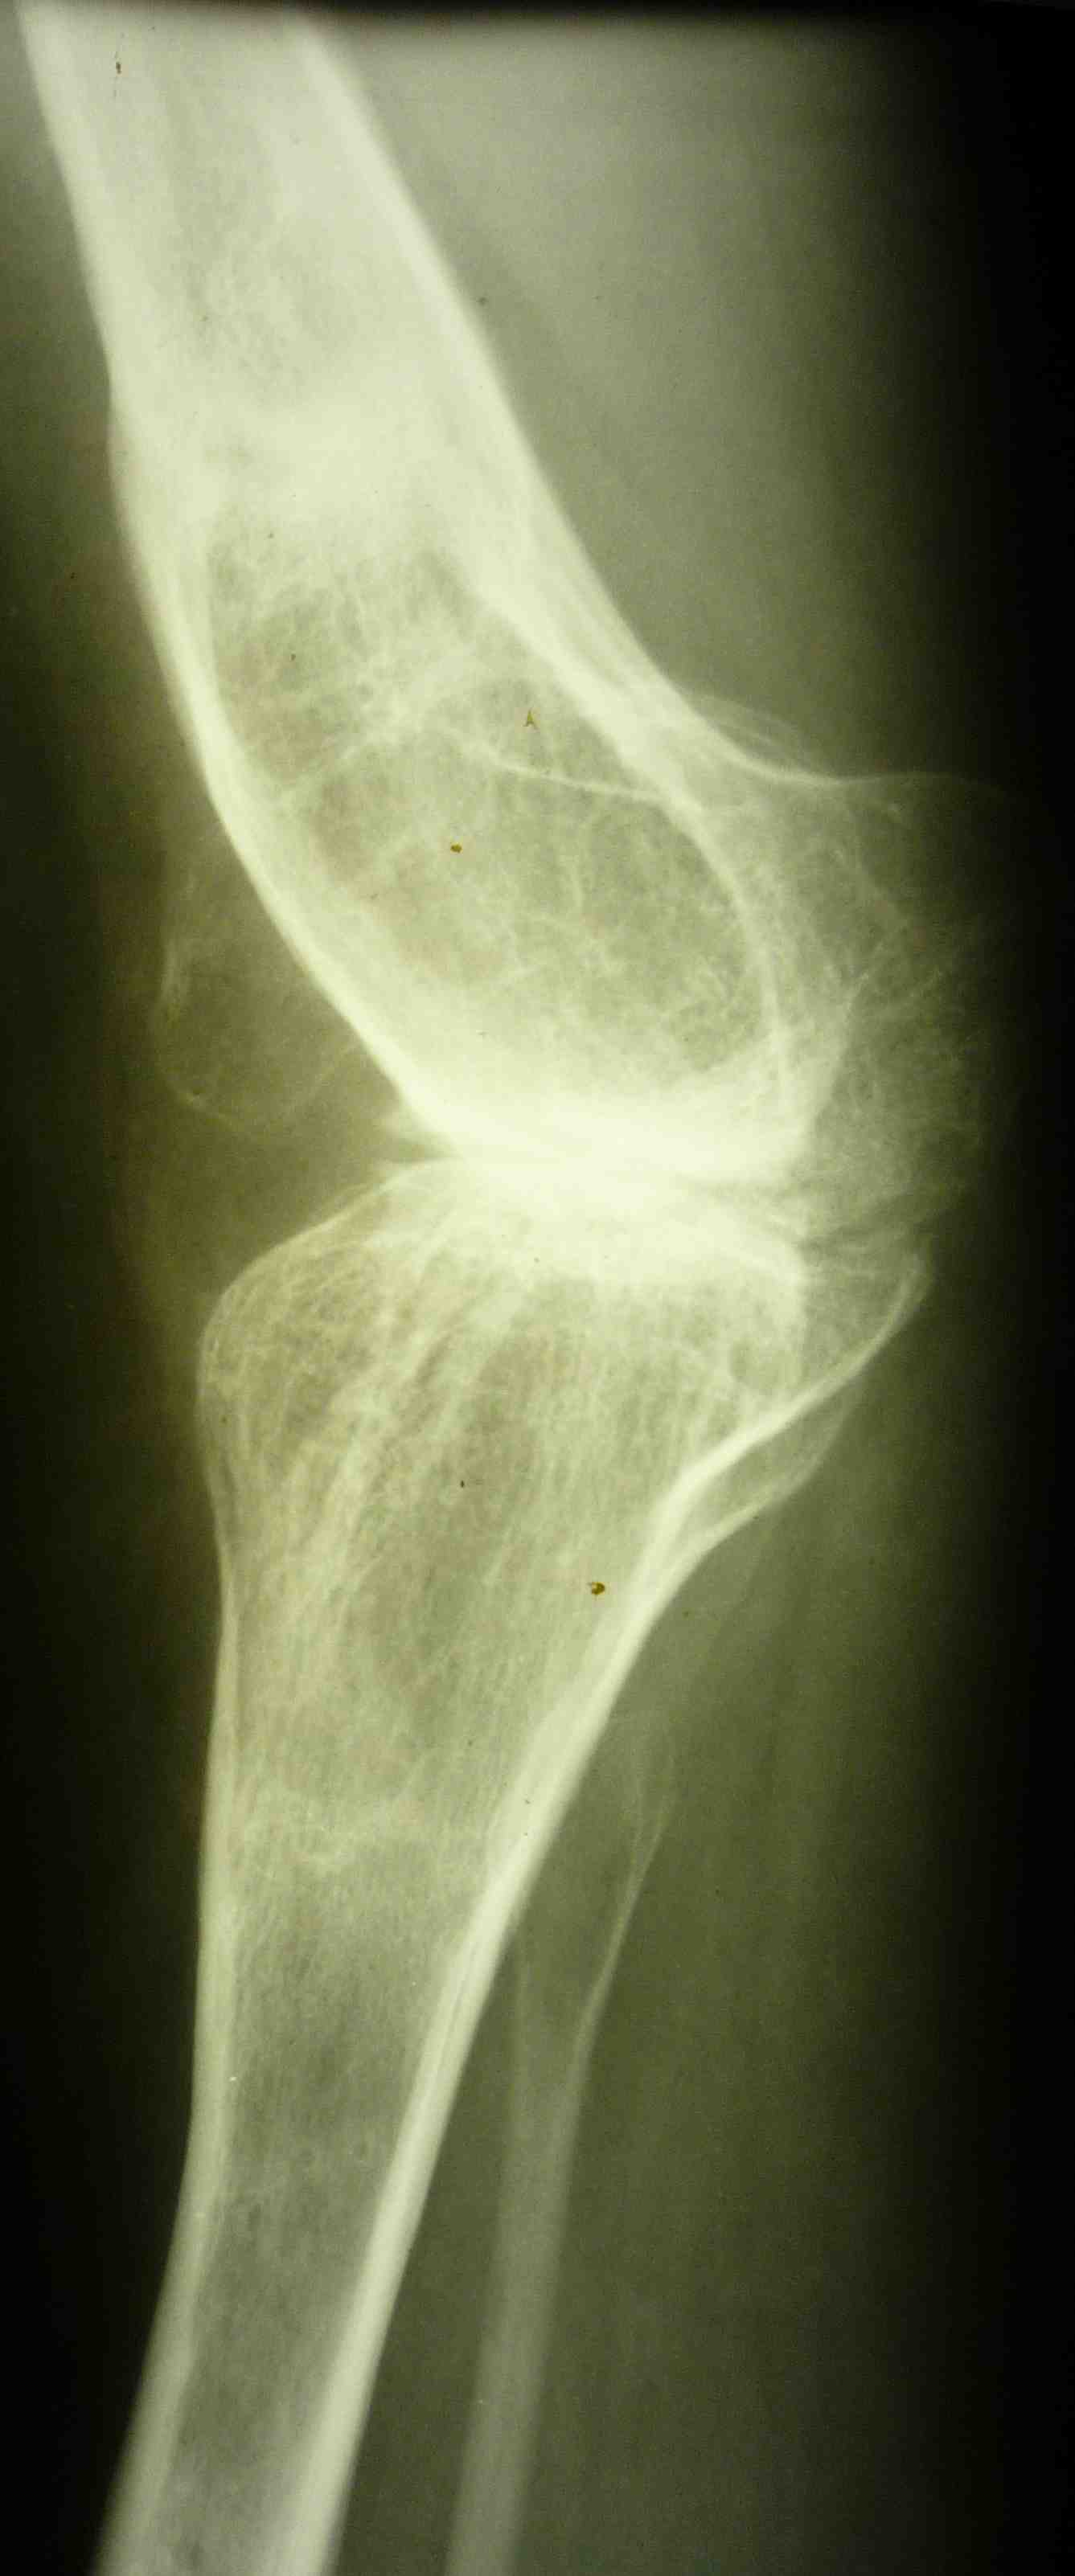

[Ortho] эндопротезирование коленного сустава

В настоящее время нет возможности сделать осевые снимки всей конечности.

Это всё чем я раполагаю на сегодняшний день.